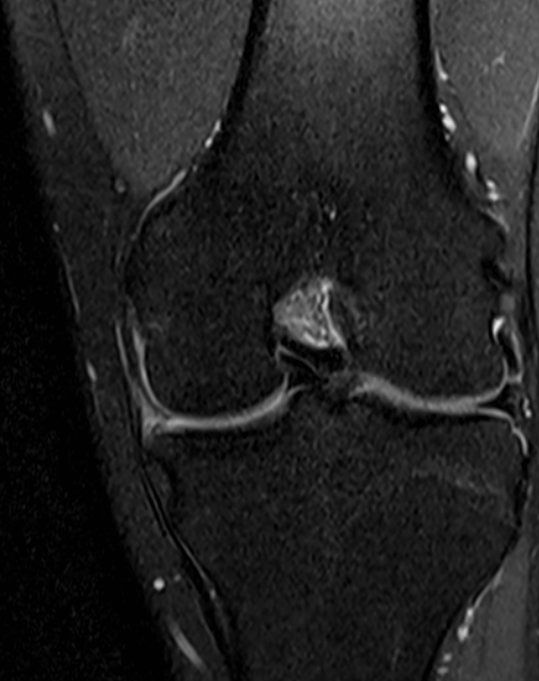

Bucket handle meniscal tear